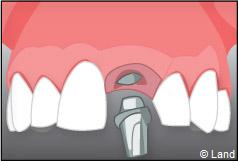

Exemple d’un implant unitaire pour remplacer une dent antérieure manquante.

Un implant dentaire est une racine artificielle, placée par le chirurgien-dentiste dans l’os alvéolaire de l’un des maxillaires en remplacement de la racine d’une dent extraite, qui servira de support à une prothèse. Sa forme est généralement cylindrique ou légèrement conique, ressemblant à une vis, en titane ou en zircone, avec une connexion au niveau supérieur, à l’emplacement de la gencive, pour permettre la pose d’un élément prothétique par vissage ou scellement. Son diamètre varie entre 3 et 5 mm et sa longueur entre 8 et 15 mm. La pose d’un implant, réalisée sous anesthésie locale, est totalement indolore. Elle se pratique au cabinet dentaire ou en clinique.

L’implant est placé dans l’os le plus souvent par vissage et doit avoir une liaison forte avec l’os. Le praticien replace alors la gencive et pose des points de suture.

À l’issue de sa mise en place chirurgicale, une bague de cicatrisation en titane peut être directement vissée sur l’implant. Ainsi une seconde chirurgie ne sera pas nécessaire pour découvrir l’implant.